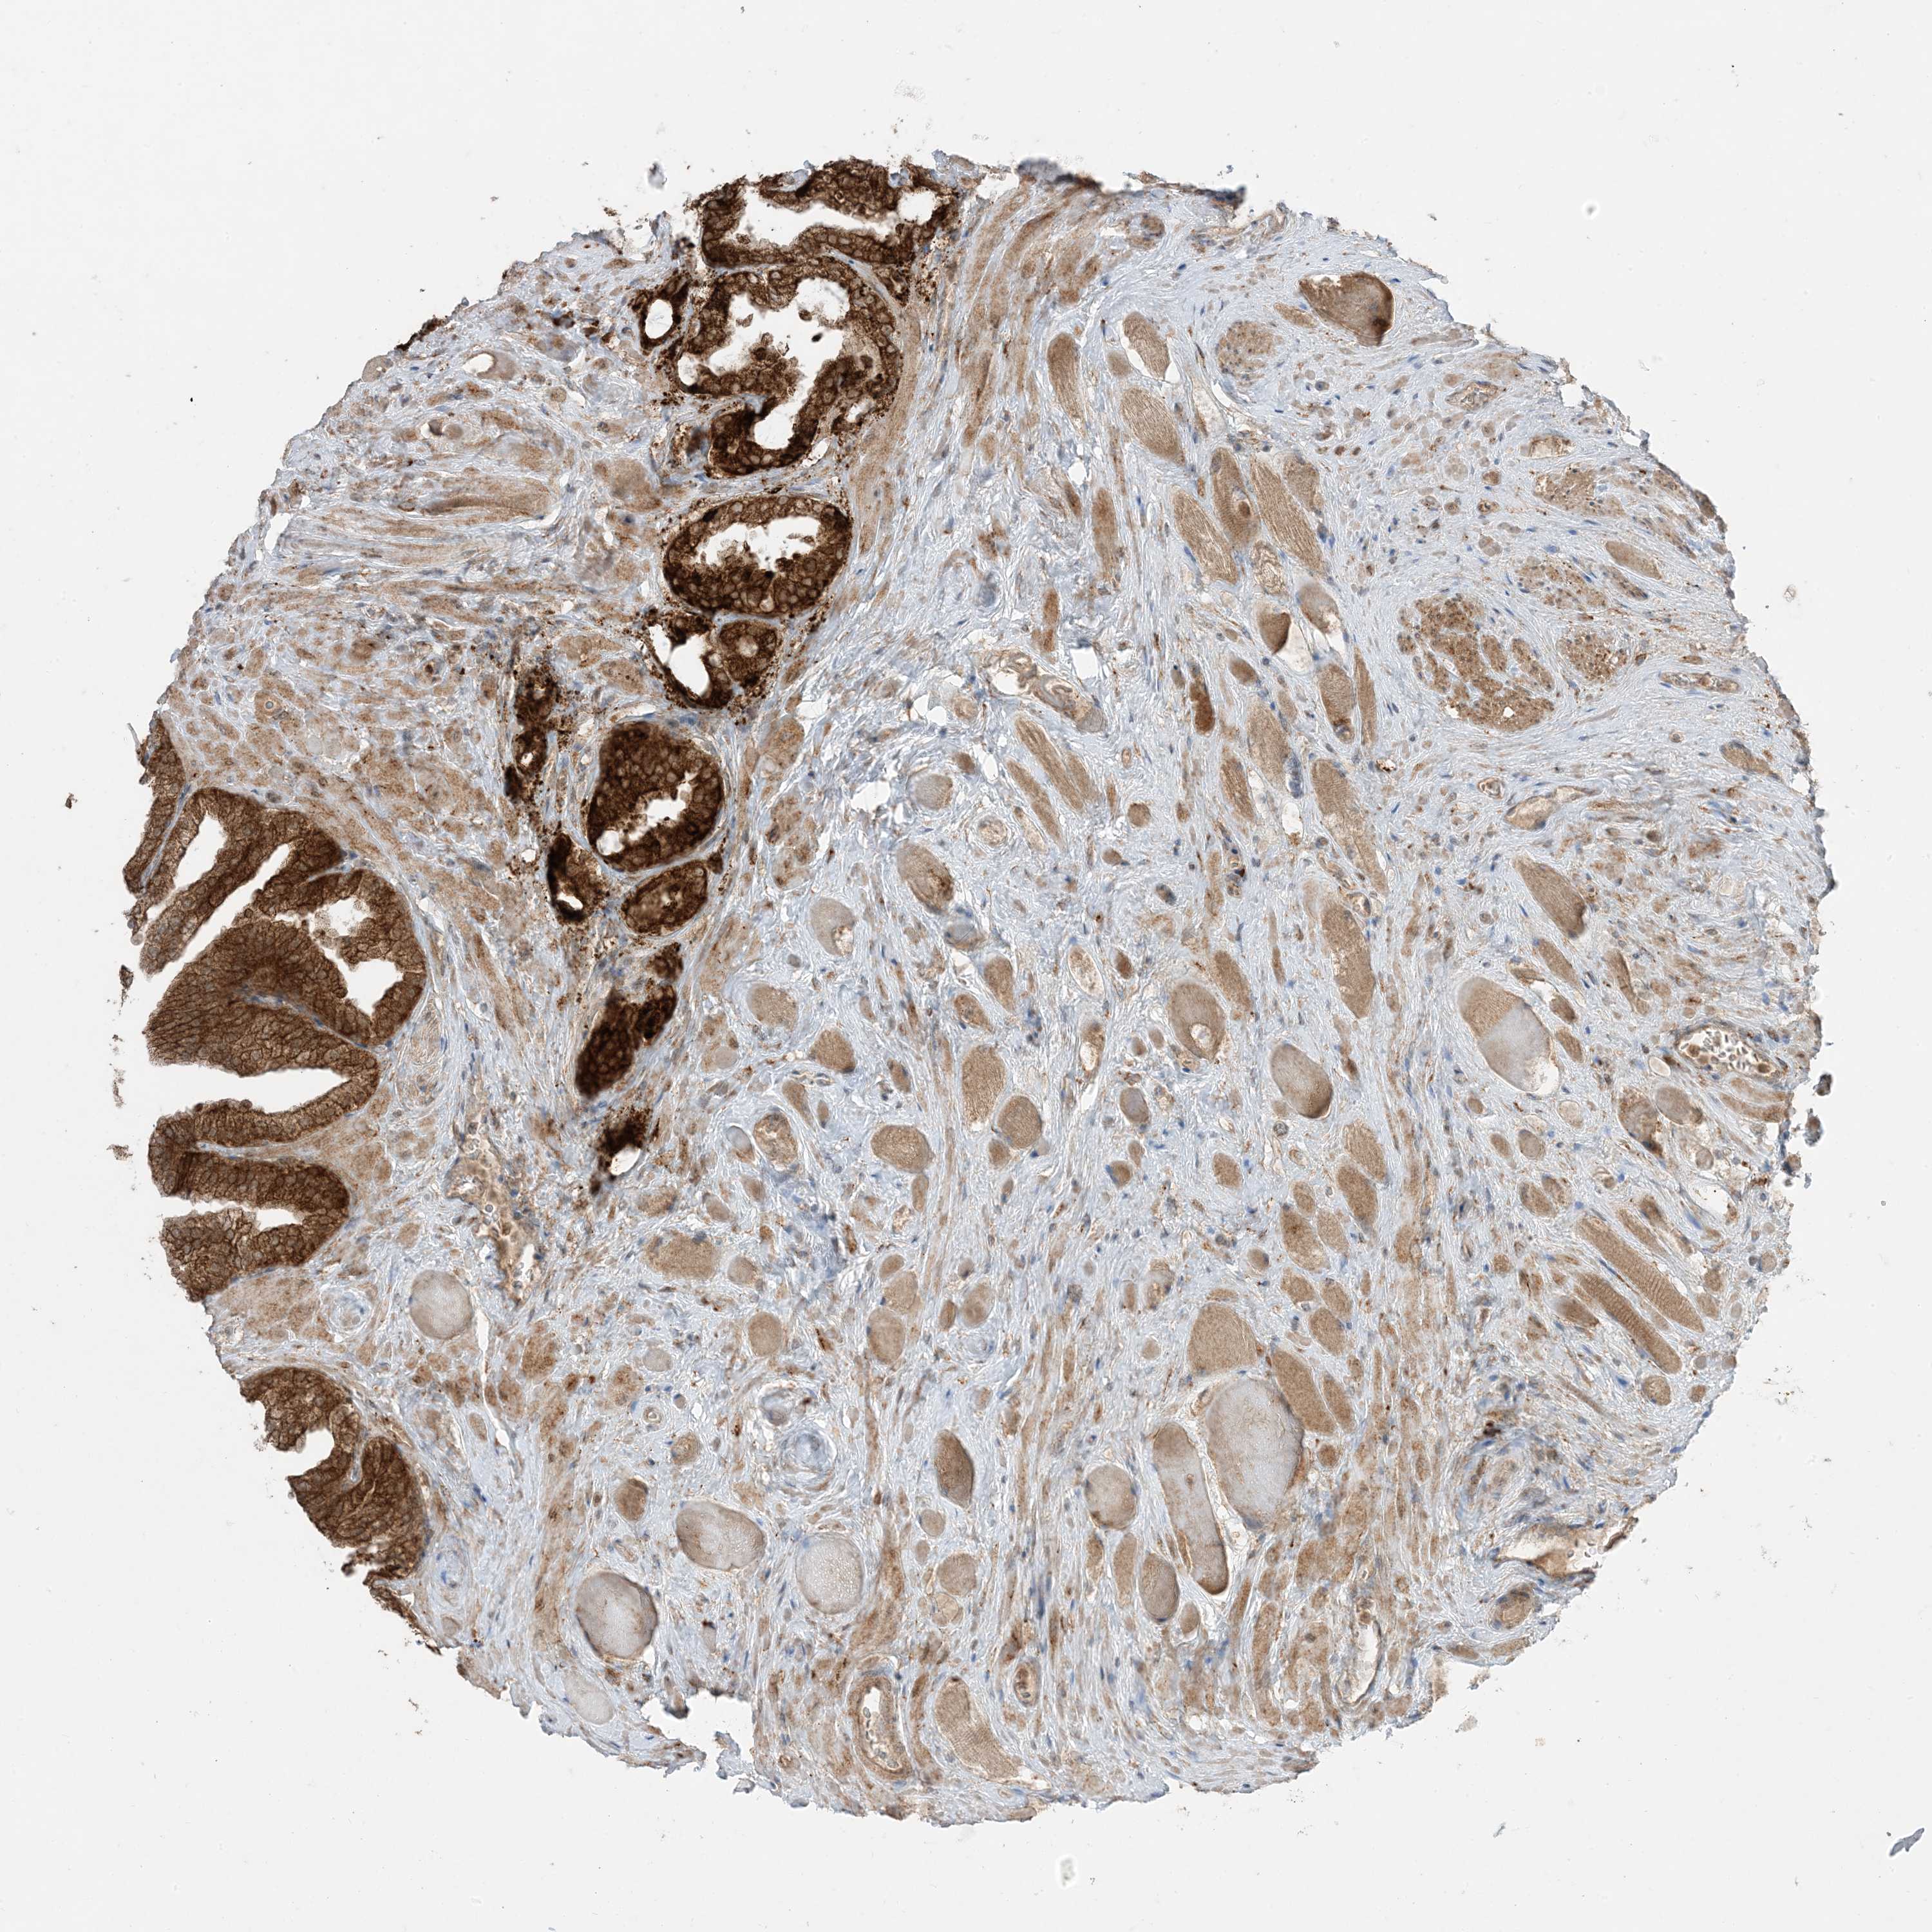

PROSTATE CANCER - Protein expressioni

A mouse-over function shows sample information and annotation data. Click on an image to view it in a full screen mode. Samples can be filtered based on level of antibody staining by selecting one or several of the following categories: high, medium, low and not detected. The assay and annotation is described here.

Antibody stainingi

Antibody staining in the annotated cell types in the current human tissue is reported as not detected, low, medium, or high, based on conventional immunohistochemistry profiling in selected tissues. This score is based on the combination of the staining intensity and fraction of stained cells.

Each image is clickable and will lead to virtual microscopy that enables deeper exploration of all samples and also displays staining intensity scores, fraction scores and subcellular localization as well as patient and tissue information for each sample.

Antibody HPA001536

Antibody CAB035996

Staining

High

Medium

Low

Not detected

Intensity

Strong

Moderate

Weak

Negative

Quantity

>75%

75%-25%

<25%

None

Location

Nuclear

Cytoplasmic/membranous

Cytoplasmic/membranous,nuclear

Adenocarcinoma, Medium grade

Adenocarcinoma, High grade

Adenocarcinoma, Low grade